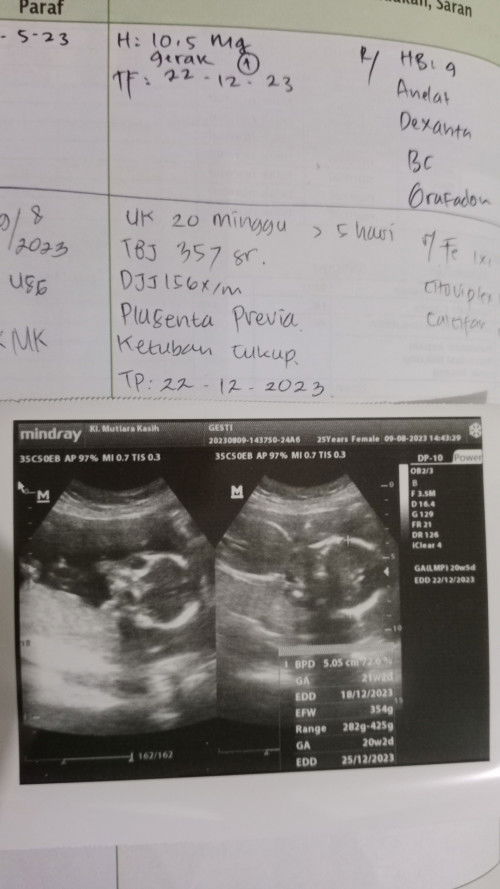

Habis USG ktanya placenta previa, apakah bisa berubah posisi bali nya ya kalo masi 5 bulan, dan upaya yg harus di lakukan apa ya biar bali nya ga menghalangi jln lahir? Mohon pencerahan nya bunda2 yg paham placenta previa 🙏🙏 Dan 1 lg katanya aku gejala anemia? Apa yg harus dilakukan klo ada gejala ini ya? Apakah ga membahayakan janin? #seriusnanya #bantusharing